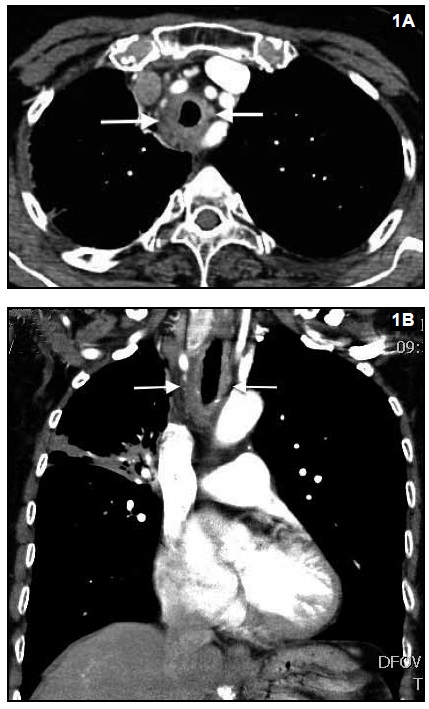

Paciente de 77 años con antecedente de tuberculosis pulmonar tratada (dos años antes) y cuadro de disnea progresivade una semana de evolución. La TC de tórax (imágenes 1Ay 1B) demostró engrosamiento difuso de la pared traqueal.

El diagnóstico diferencial del engrosamiento difuso de la pared de la tráquea incluye: entidades infecciosas (histoplasmosis - tuberculosis), inflamatorias (sarcoidosis, poliangeítis con granulomatosis) y entidades de naturaleza diversa (amiloidosis, policondritis recidivante y traqueobroncopatíaosteocondroplástica). La biopsia de la pared bronquial confirmó el diagnóstico de tuberculosis.

La tuberculosis traqueobronquial se caracteriza por engrosamiento concéntrico de la pared con estrechez irregular del lumen y puede asociarse a mediastinitis y/o adenomegalias mediastinales.